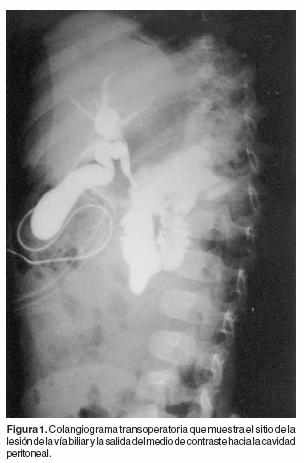

Paciente femenino de 11 meses de edad quien inició su padecimiento dos semanas antes de su ingreso con fiebre no cuantificada, evacuaciones liquidas en número de cuatro al día y vómito, motivo por el cual fue internada en un hospital general iniciándose tratamiento con alimentación endovenosa y antimicrobianos. Tres días después presentó distensión abdominal y ausencia de evacuaciones, motivo por el que fue enviada a nuestra unidad hospitalaria. A la exploración clínica se encontró sin ictericia, bien hidratada, irritable y con sonda nasogástrica instalada a través de la cual drenaba líquido biliar. El abdomen era globoso con perímetro de 52 cm, doloroso a la palpación superficial y peristalsis disminuida. La citología hemática mostró leucocitosis de 12,900, neutrófilos de 58%, linfocitos de 30% y hemoglobina de10.0 grs%. Aproximadamente 4 horas después, se efectuó laparotomía exploradora encontrándose l000 cc de líquido biliar en la cavidad peritoneal y gotas lipoidicas sobrenadantes, por lo que se exploró la vía biliar en donde se encontró una perforación de 1.2 por 0.9 cms en la unión de los conductos hepático común, cístico y colédoco. Con este hallazgo se optó por reparar la lesión y colocar en su interior de la vía biliar una sonda calibre 5F. La evolución del gasto por la sonda descendió de 100 a 5 cc cada 24 horas; en el octavo día se efectuó una colangiografía de control en la que muestra la fuga del medio de contraste (Figura 1) y dilatación de la vía biliar principal, visualización del conducto de Wirsung y en la confluencia de ambos, la estenosis producto de la colangitis crónica (Figura 2). Se inició la vía oral y fue dada de alta al 12avo día de estancia hospitalaria con citología hemática y pruebas de función hepática normales.